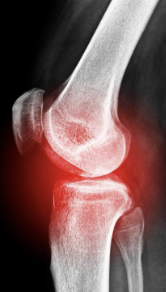

무릎 관절염 증상 원인 치료방법(+좋은 음식과 운동) 알아봐요. 무릎 관절염은 무릎 관절의 연골 파괴, 염증 및 변형으로 인해 발생하는 질환입니다. 증상으로는 통증, 감각 이상, 충동성 통증, 강직성 및 관절의 이상운동이 포함된다. 주요 위험 인자로는 노화, 비만, 골관절염, 부상 및 과도한 사용 등이 있습니다. 진단은 증상 및 영상진단 검사를 통해 이루어지며, 치료는 수술, 약물 치료, 생활습관 변화, 물리 치료 등이 있습니다. 무릎 관절염은 진행성이며, 조기 발견 및 치료가 중요합니다. 예방을 위해서는 체중 조절, 적극적인 운동, 관절 보호를 위한 적절한 신발 착용 등이 필요합니다.

무릎 관절염 증상

무릎 관절염 증상은 천천히 진행되며, 다음과 같은 증상이 나타납니다.

- 통증: 무릎 관절 주위에 통증이 나타나며, 장시간 서 있거나 앉아 있을 때 악화됩니다. 일부 사람들은 밤에도 통증을 느낄 수 있습니다.

- 관절 이상운동: 무릎 관절에서 뻐근함이나 강직함을 느낄 수 있습니다. 이러한 강직성으로 인해 보행이 어려워질 수 있습니다.

- 충동성 통증: 무릎을 갑자기 움직였을 때 발생하는 통증으로, 발작적인 통증이 나타납니다.

- 염증: 무릎 주위의 염증은 붓기와 따끔함을 유발합니다.

- 감각 이상: 무릎 관절에 통증과 함께 무릎 주위의 피부 감각이 변화할 수 있습니다.